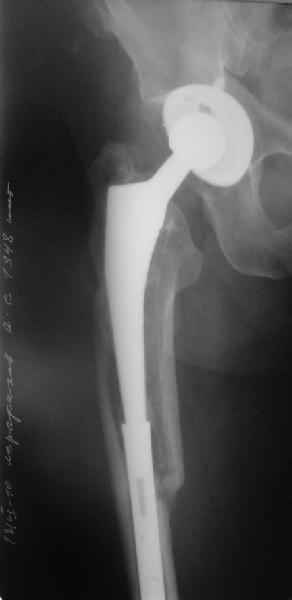

Произведено закрытое удлинение ножки эндопротеза с помощью ретроградного интрамедуллярного стержня. Продолжительность операции 3 часа. Два из них закрытое восстановление длины бедра диистрактором

таз-бедро.

А нельзя ли увидеть и профиль бедра на всем протяжении, т.е. и весь протез, и весь стержень? И фас бы с коленом.

Спасибо!

новые снимки